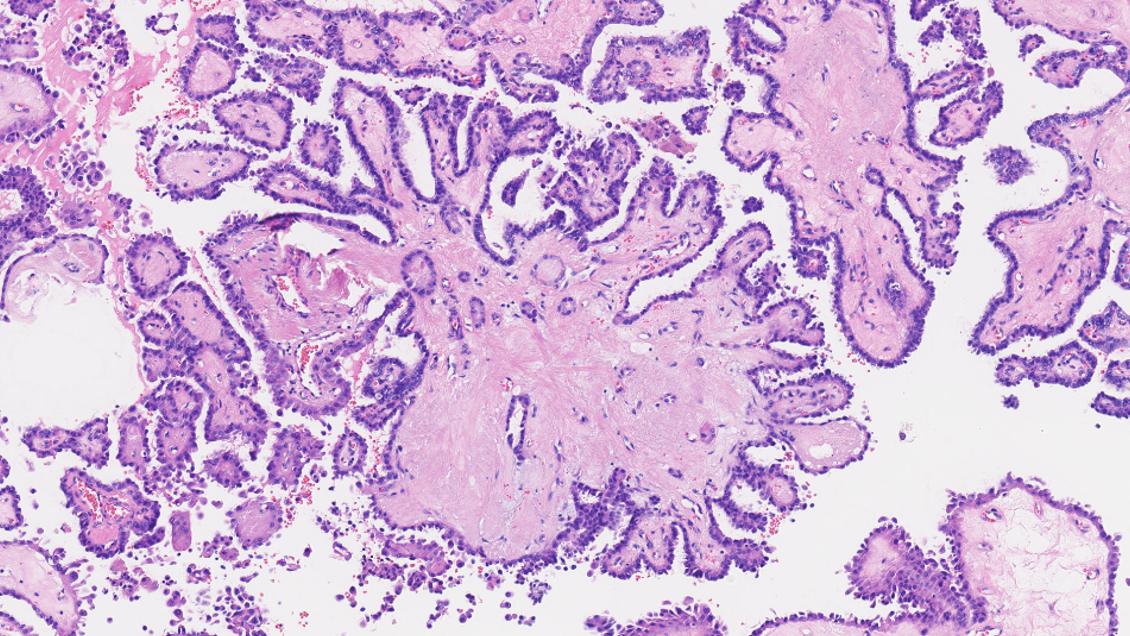

一、检测背景随着全球首款靶向Claudin18.2(CLDN18.2)的抗体药物佐妥昔单抗在国内外上市,胃癌治疗进入精准靶向新时代。中国临床肿瘤学会(ChineseSocietyofClinicalOncology,CSCO)、美国国立综合癌症网络(NationalComprehensiveCancerNetwork,NCCN)、欧洲肿瘤内科学会(EuropeanSocietyofMedicalOncology,ESMO)等权威指南以及《胃癌Claudin18.2临床检测专家共识(2025版)》均推荐对胃/胃食管交界处(Gastroesophagealjunction,GEJ)腺癌进行CLDN18.2检测,为精准筛选靶向治疗获益人群提供关键依据,为晚期胃癌患者带来新的生存希望[1-3]。研究证实约40%的胃/GEJ腺癌患者为CLDN18.2阳性表达,提示这部分患者可能从靶向治疗中获益,其中接受佐妥昔单抗联合化疗方案的患者,疾病进展或死亡风险降低25%至31%,显著延长无进展生存期和总生存期。在胃癌的临床实践中,CLDN18.2免疫组织化学(immunohistochemistry,IHC)检测已成为评估抗CLDN18.2靶向治疗适用性的重要手段。二、适用人群(主要包括但不限于)初治晚期胃/胃食管交界处腺癌患者;HER2阴性寻求新靶向治疗机会者;传统治疗效果不佳的难治性患者。三、技术保障检测抗体:Claudin18.2(43-14A)。检测平台:Ventana全自动免疫组化仪。判读标准:严格按照《胃癌Claudin18.2临床检测专家共识(2025版)》强推荐的判读标准,将≥75%的肿瘤细胞具有2+/3+强度膜染色判读为阳性/高表达,并出具明确的阳性/阴性及具体表达水平的报告,如“Claudin18.2阳性(3+,90%)”、“Claudin18.2阴性(2+,30%)”等。四、检测结果判读示例图①-④胃腺癌肿瘤细胞及周围正常黏膜腺体Claudin18.2的表达情况①非肿瘤性胃黏膜腺体(右半部分)为细胞膜强阳性着色,肿瘤细胞(左半部分)呈2+细胞膜环形阳性着色;②非肿瘤性胃黏膜腺体(右半部分)为细胞膜强阳性着色,肿瘤细胞(左半部分)呈2+细胞膜基底外侧/外侧阳性着色;③、④肿瘤细胞呈3+细胞膜环形阳性着色参考文献:《胃癌Claudin18.2临床检测专家共识(2025版)》专家委员会.胃癌Claudin18.2临床检测专家共识(2025版)[J].中华病理学杂志,2025;54(7):718-725.doi:10.3760/cma.j.cn112151-20250408-00245.ShitaraK,LordickF,BangYJ,etal.ZolbetuximabplusmFOLFOX6inpatientswithCLDN18.2-positive,HER2-negative,untreated,locallyadvancedunresectablemetastaticgastricgastro-oesophagealjunctionadenocarcinoma(SPOTLIGHT):amulticentre,randomised,double-blind,phase3trial.Lancet,2023;402(10398):1655-1668.PMID:37068504.doi:10.1016/S0140-6736(23)00620-7.ShahMA,ShitaraK,AjaniJA,etal.ZolbetuximabplusCAPOXinCLDN18.2-positivegastricgastroesophagealjunctionadenocarcinoma:therandomized,phase3GLOWtrial.NatMed,2023;29(8):2133-2141.PMID:37524953.doi:10.1038/s41591-023-02465-7.备注:本文在成稿后经由元宝大语言模型进行语言润色与逻辑优化,旨在提升表达的准确性与流畅性,核心观点与内容均由作者独立完成。‌‌